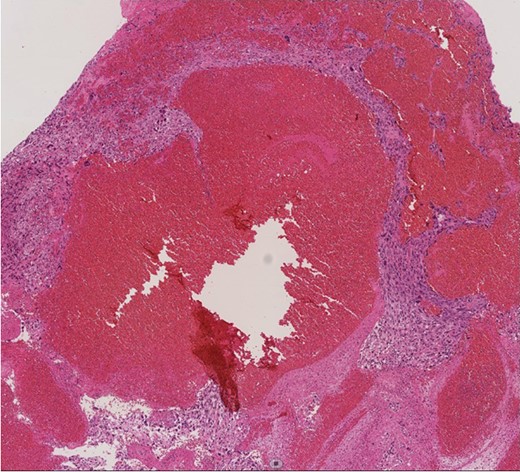

Histopathological image (×100). Histologic analysis of the specimen shows high-grade undifferentiated sarcoma due to polymorphism with mitoses and a polychromatic inner lining. Necrotic tissue and thrombi are also present in the tumor, with invasion into the fibrous intima of the pulmonary artery.